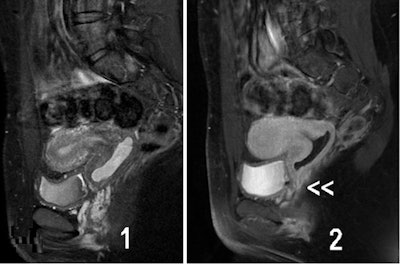

![Urogenital sinus anomalies. MR images [(1) T1- and (2) T2-weighted fat-suppressed images in the sagittal plane] show a retrovesical blind vagina with apparent inferior half atresia and undetected fistula tract to the bladder (](https://img.auntminnieeurope.com/files/base/smg/all/image/2016/08/ame.2016_08_26_16_04_51_413_female_genital_malformationspic3.png?auto=format%2Ccompress&fit=max&q=70&w=400)